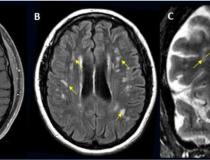

Significant alterations in the brain’s white matter in adolescents with ASD. Image courtesy of RSNA

-